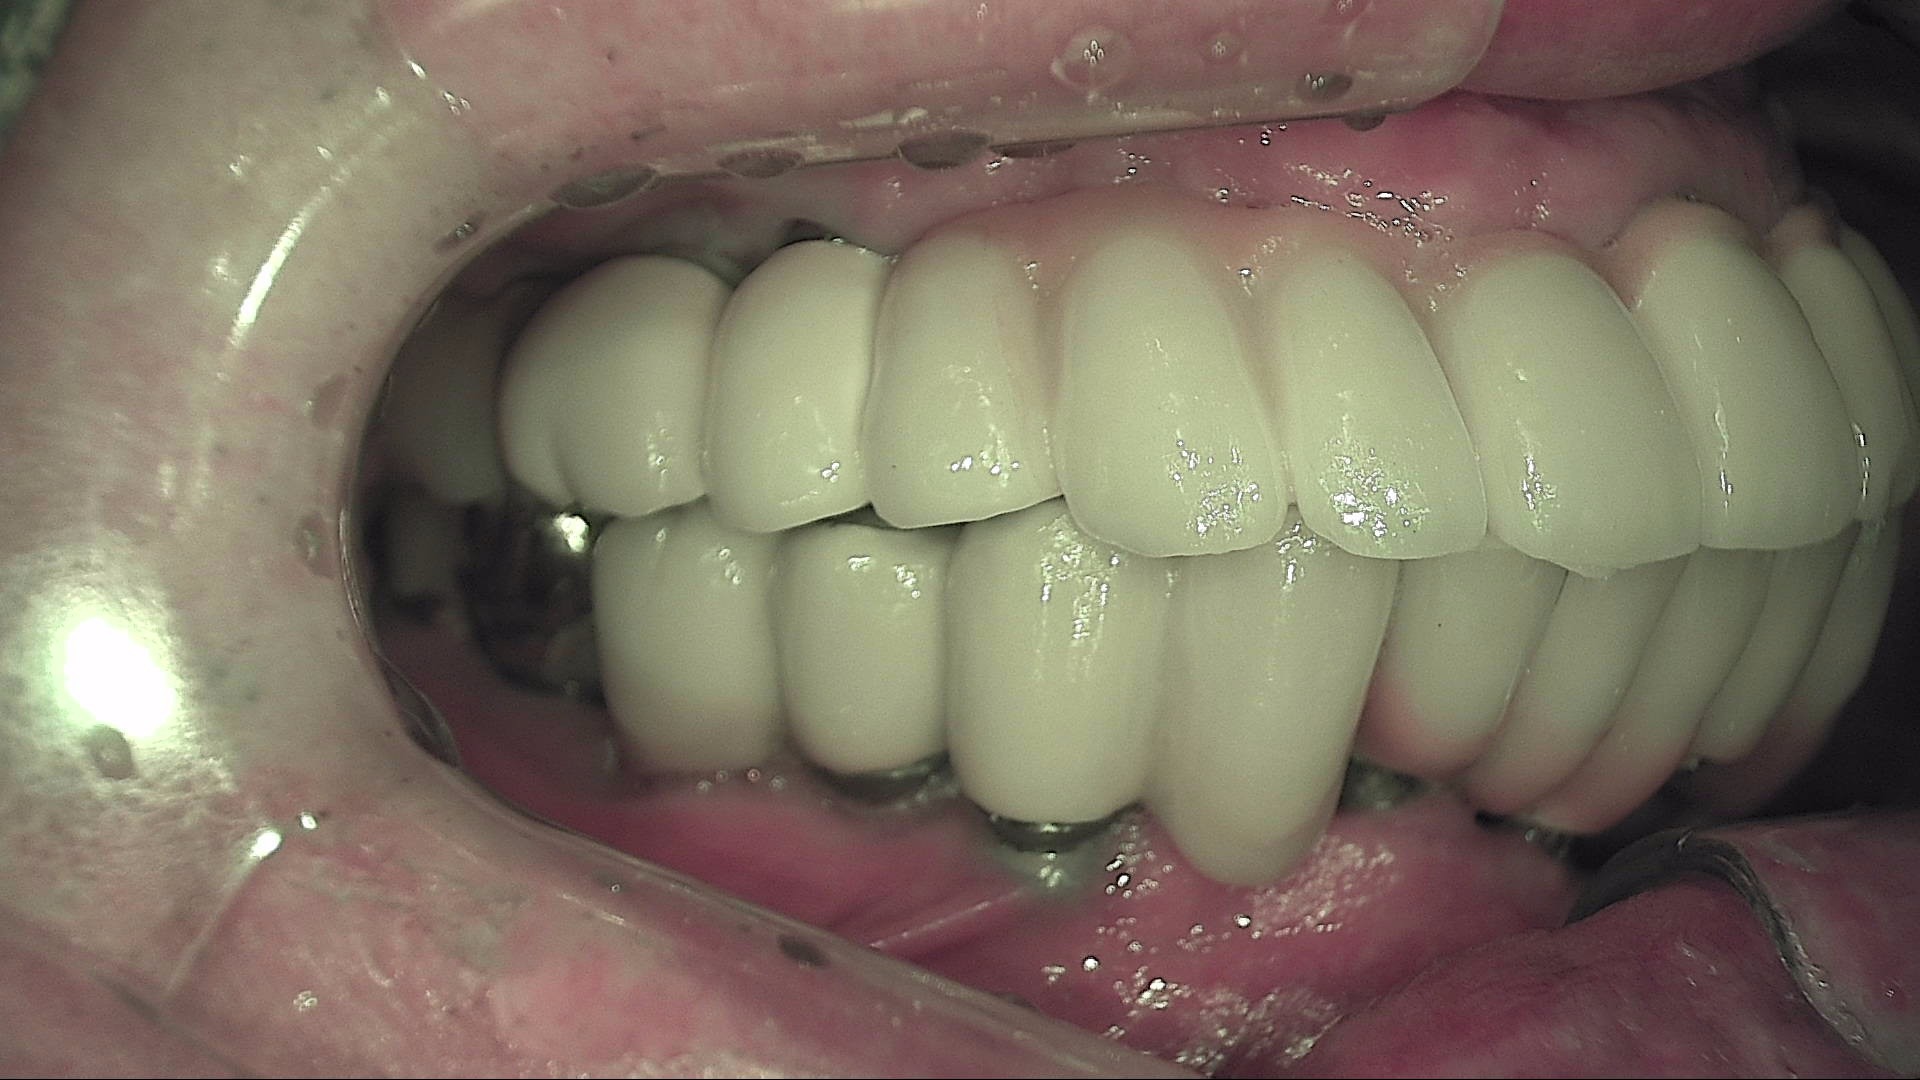

Crack

큐레이캠프로, 큐레이펜씨